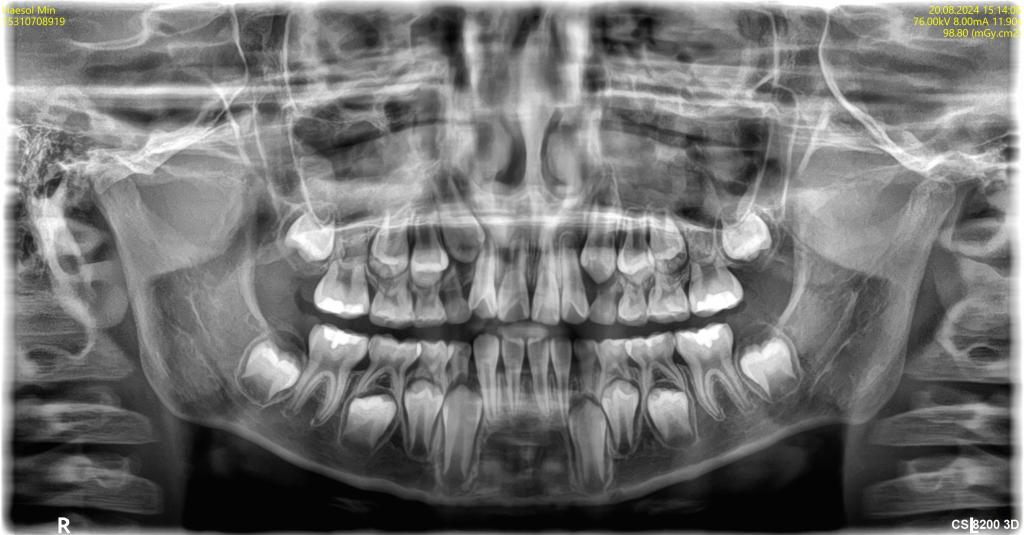

치아교정 및 임플란트 질문입니다..

진작 빨리 치료를 했어야했는데 정말 여기저기 다니면서 고민만 하다가 시간이 훌쩍 지나버렸어요 교정 방법이 너무 다른데 제 치아가 너무 어려운(?) 케이스 같아서.. 부작용+외모변화 등 걱정이 많습니다 사실 임플...

전문의 답변 1